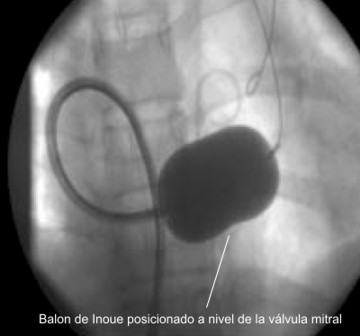

La valvuloplastia, es un procedimiento de Terapia Endovascular que tienen como propósito aliviar una estenosis valvular, en este procedimiento se usan balones especialmente diseñados para este fin (Inoue).

Actualmente, la Valvuloplastía percutánea con balones es el tratamiento de elección en pacientes con estenosis valvular sintomáticos y en ausencia de contraindicaciones, pero lo más frecuente es que se realice sobre la válvula mitral.

La Valvuloplastía percutánea con balón en la Estenosis mitral, salvo contraindicaciones, es un procedimiento efectivo, que además evita los costos y los riesgos de una cirugía mayor.

Valvuloplastia con balón Inoue